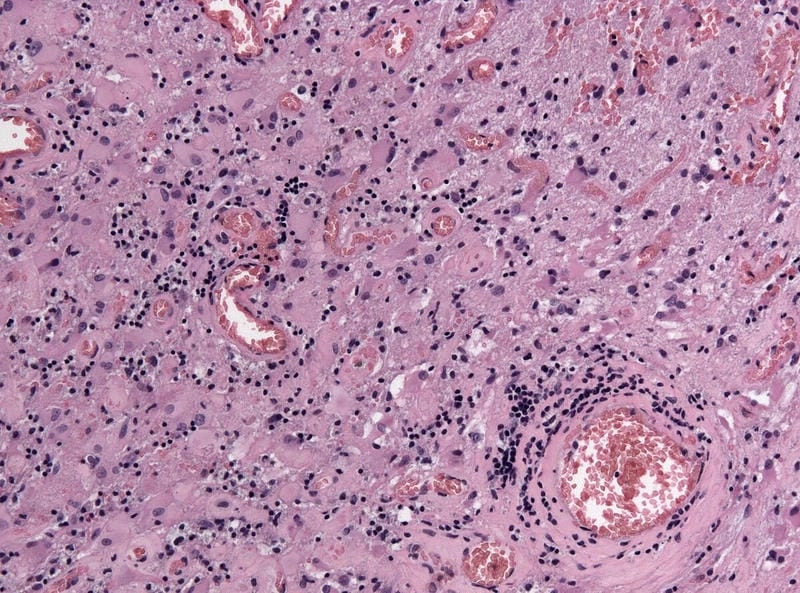

Image description of La Crosse Encephalitis

La Crosse Encephalitis is a rare viral disease spread by mosquitoes. It primarily affects children and can lead to fever, headache, seizures, and neurological complications in severe cases.